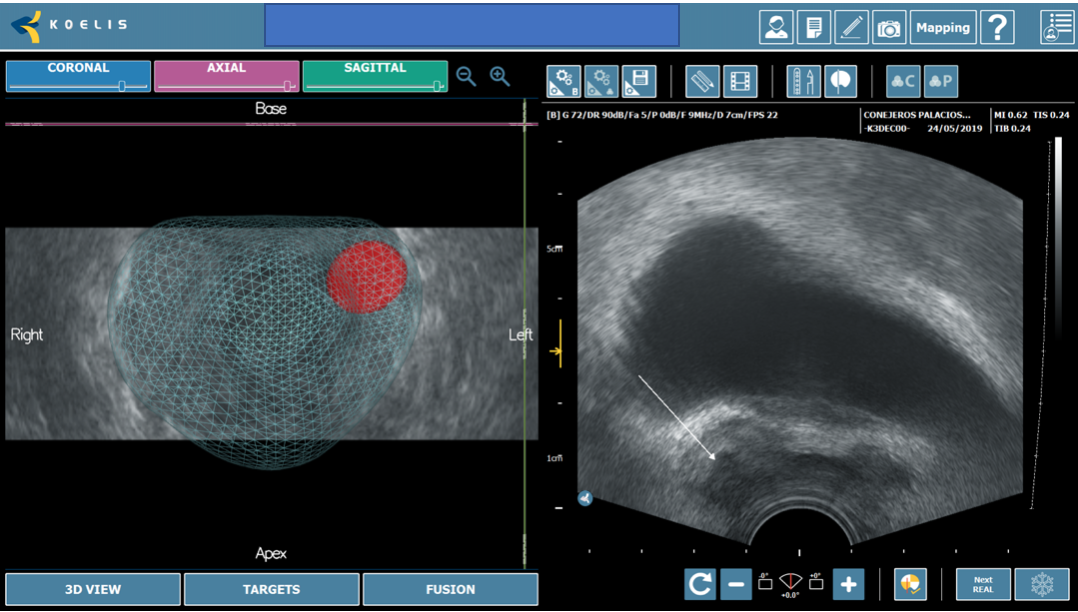

TRUS ofrece la capacidad de obtener imágenes en tiempo real, pero está limitada por una resolución espacial deficiente y una baja sensibilidad para el cáncer de próstata, ya que las lesiones a menudo pueden parecer isoecoicas en las imágenes de TRUS, lo que hace que sea difícil distinguirlas del fondo (1). Por el contrario, las imágenes de RM presentan lesiones prostáticas con detalles precisos y tienen una alta sensibilidad, pero no ofrecen la capacidad de adquisición de imágenes en tiempo real y orientación para la biopsia de manera oportuna o rentable. Los desarrolladores han creado estratégicamente plataformas de «fusión» para combinar imágenes de MRI y TRUS, lo que permite al urólogo acceso a la información esencial que ofrecen ambas modalidades (2). Una biopsia de fusión dirigida permite el muestreo de regiones específicas dentro de la próstata con lesiones identificadas en MRI, proporcionando así la posibilidad futura de eludir la necesidad de biopsias aleatorias «ciegas» en toda la glándula. (Figura 1).

Fig. 1. Biopsia por fusión. Correlación entre zona hipoecoica marcada en base derecha (flecha) con zona sospechosa marcada en resonancia (estrella).